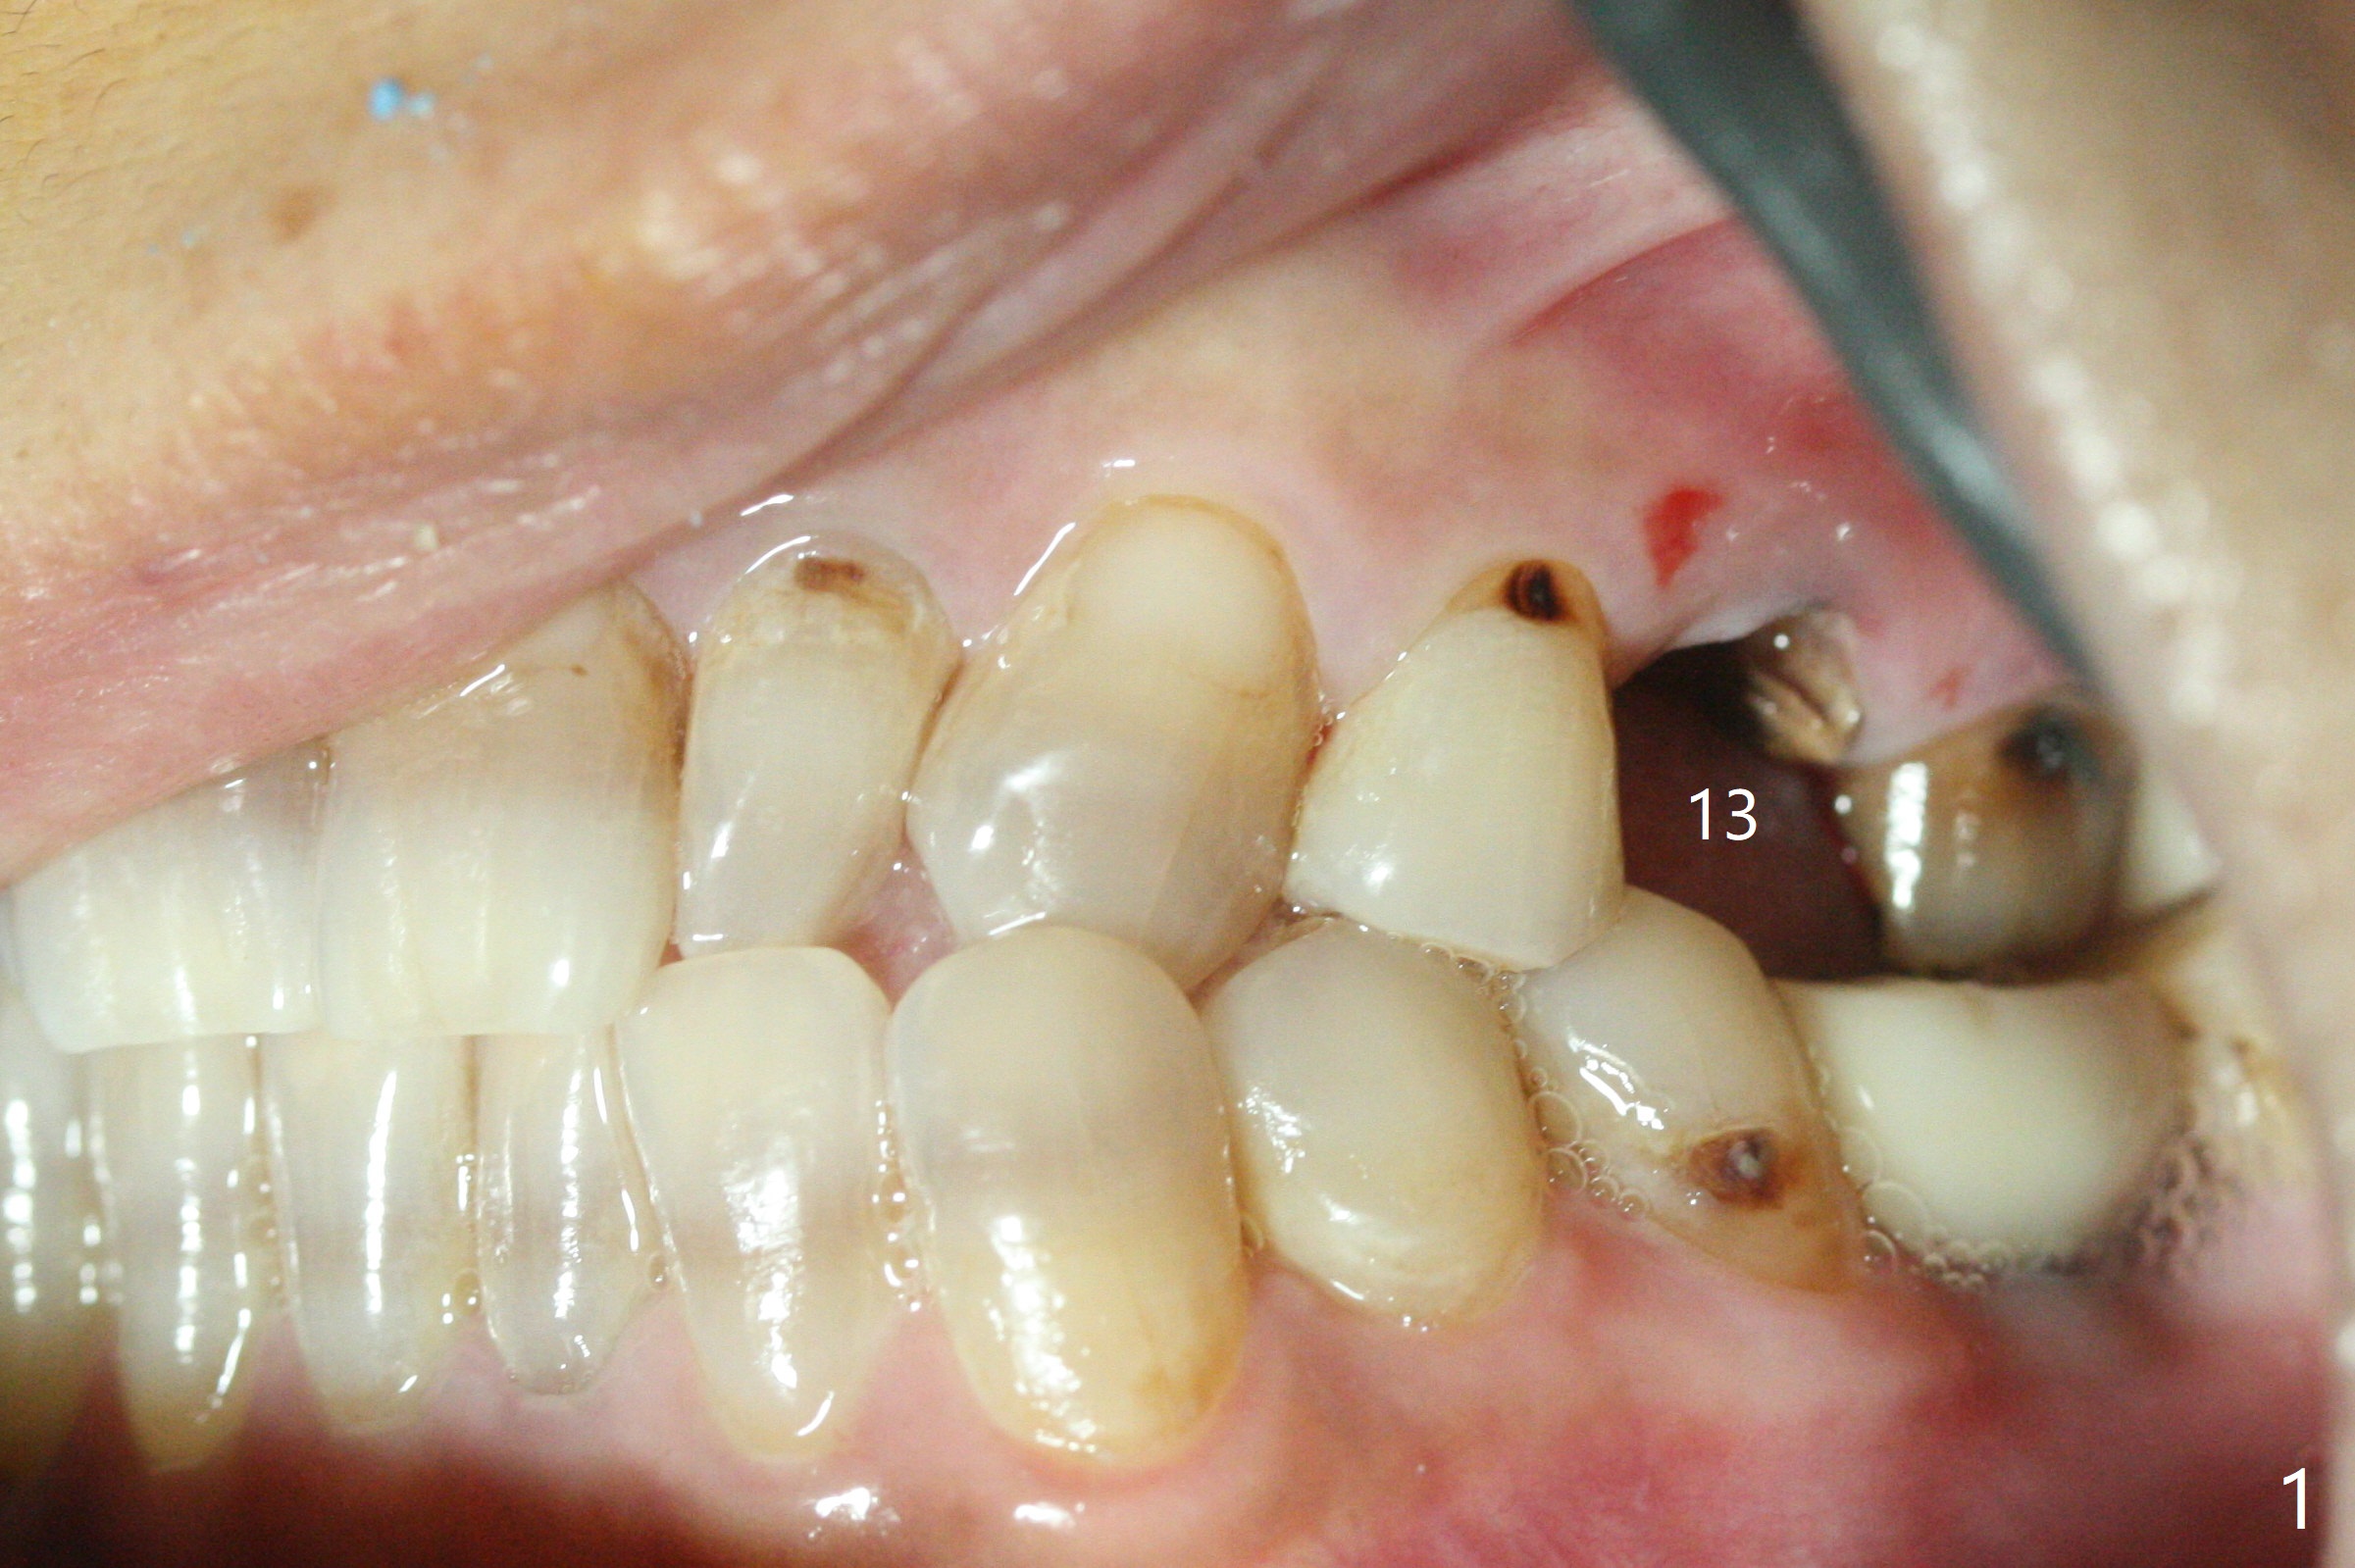

The patient with the anterior cross bite at the left lateral and canine and incipient Class V caries returns to clinic for #13 residual root extraction (Fig.1,2). There is no quality root structure (Fig.2) or space (Fig.3) for socket sheath. Two amalgam carriers of Vanilla is inserted and pushed by the 4x11 mm dummy implant for sinus lift (Fig.4 *). When the same sized final implant (4x11 mm) is placed, a 5.5 mm bone profile drill is used to trim the proximal crests (Fig.5 * sticky bone packed in the buccal and palatal gaps). In fact the implant turns when a 4.5x4(3) mm pair abutment is tightened. The implant is backed up; with a healing screw, sticky bone is placed (Fig.6 *) and then covered with a piece of PRF and a part of GEM cap. The wound is sutured with 4-0 PGA; periodontal dressing is applied. The implant is somewhat over-seated without the bone graft covering the apical end of the implant (Fig.7, as compared to Fig.4). A 4.5 mm implant should be placed. The GEM Cap appears to be absent 9 days postop, while the periodontal dressing dislodged in 1 week (Fig.8). It appears that the existing abutment at #15 is incompletely seated (Fig.3, 5.5x4(2) mm). After use of 5.5 and 6.0 mm bone profile drills, a 5x4(3) mm abutment is placed with 35 Ncm torque. In fact the bone graft coronal to the implant remains (Fig.9 *) in spite of apparent loss of the overlying PRF and GEM cap (Fig.8). After use of a 4.6 mm profile drill, a 5.5x3 mm healing abutment is placed 4.5 months postop (Fig.10). Without a provisional at #13 for ~ 4 months, there is a gap between crowns at #14 and 15 (not shown due to angulation). Impression is taken for #13 crown fabrication 5.5 months postop and for #15 crown repair (addition of porcelain for the mesial contact, Fig.11). It appears critical for a provisional to maintain the position of the neighboring tooth.